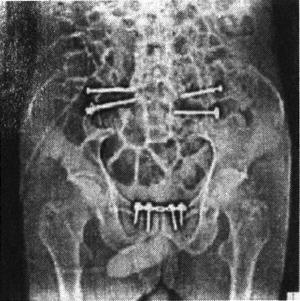

术后处理:术后第1天即允许患者半卧位,肌肉力量训练在术后第1天进行。第3天即开始扶拐不负重或部分负重行走。持续抵抗重力训练6周,随后逐渐过渡到完全负重,争取在术后3个月弃拐独立行走。

图13-61 骶髂关节螺钉固定术后X光片